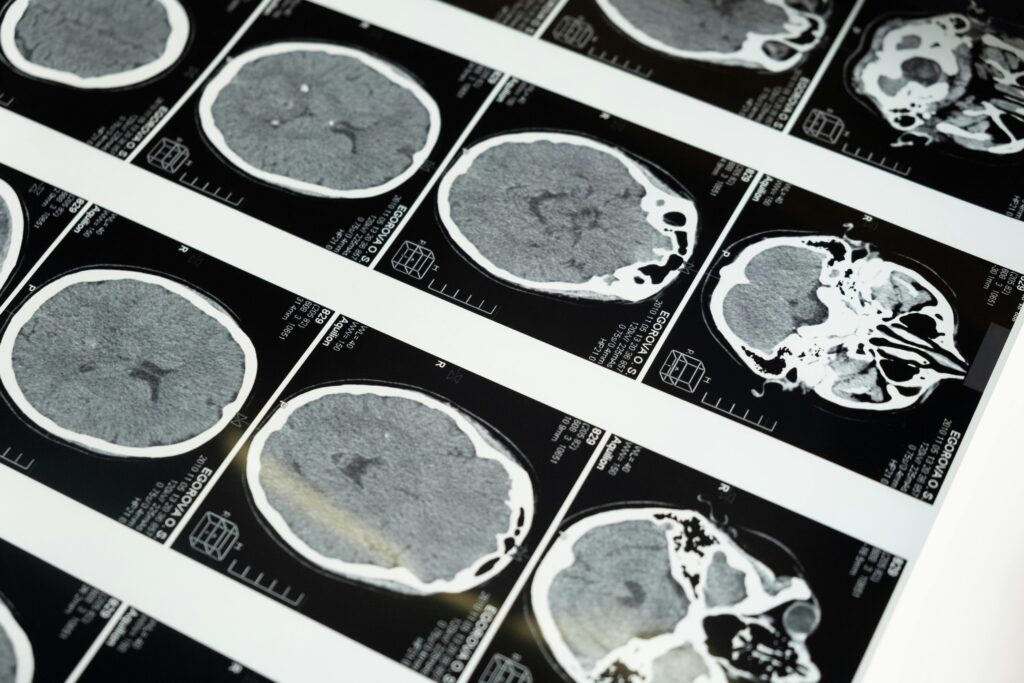

Glioblastoma is the most aggressive and deadly cancerous brain tumor known to medical science. This form of brain cancer affects approximately 3,200 people yearly in the United Kingdom. So when Ben Trotman was diagnosed in 2022, his family braced for the worst prognosis. Typically, patients with Glioblastoma live an average of 15 months after diagnosis, and 6.9% survive up to 5 years.

However, after receiving a remarkable new experimental immunotherapy treatment, Ben Trotman’s glioblastoma brain tumor has completely disappeared. This drug, a targeted immunotherapy treatment called Ipilimumab, represents a breakthrough that could bring new hope for glioblastoma patients. Trotman was treated by UCLH medical oncologist DR. Paul Mulholland at The National Hospital for Neurology and Neurosurgery at UCLH. Due to the lack of patients, Trotman was the only patient enrolled in the NeAT-GLIO trial, receiving ipilimumab.

Ben Trotman received his glioblastoma diagnosis in October 2022 at age 40. The devastating news meant facing an average survival rate of just 15 months after diagnosis. Trotman also received radiation and chemotherapy. However, thanks to this experimental drug, Trotman gained his life back.